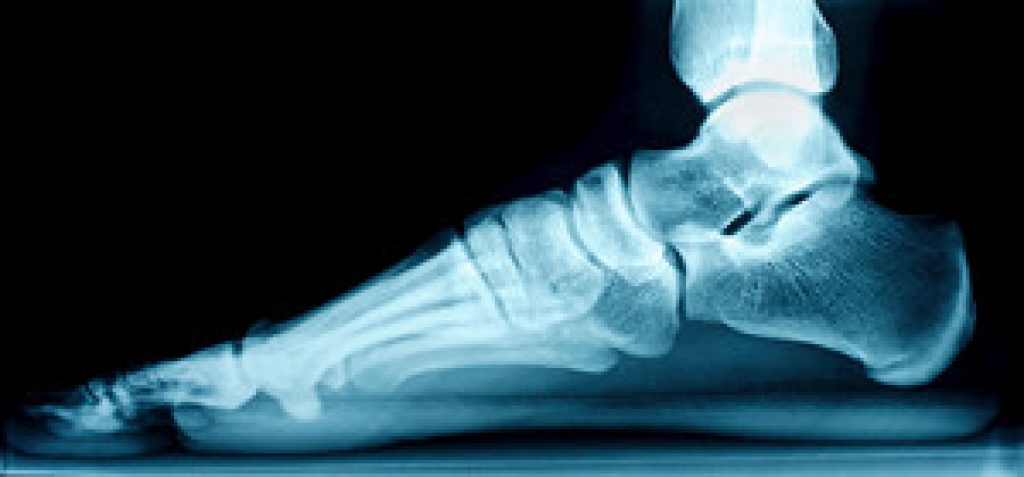

If you feel pain or discomfort in the midfoot area, you may have developed stress fractures in the 2nd and 3rd metatarsal bones of the foot. The most common cause is repetitive walking for long periods. This condition, sometimes called “march fractures,” is common after a trip with prolonged walks or hikes, in overtraining for a marathon type of event, or from military recruitment exercises. Other causes include a change in foot shape—perhaps the result of bunions—that may overload the midfoot bones, and osteoporosis, which is a weakening of the bones as the result of low bone density. Symptoms include pain and swelling, as well as tenderness to the touch, which could worsen if the activity is continued. As with all painful foot conditions, it is a good idea to schedule a visit to a podiatrist for a complete checkup, which will likely include X-rays or other imaging tests to see the extent of the injury. In the meantime, avoid walking or bearing weight on the affected foot as much as possible to help it heal more quickly.

Stress fractures occur when there is a tiny crack within a bone. To learn more, contact one of our podiatrists from Toe-Tal Family Foot & Wound Care Professionals . Our doctors can provide the care you need to keep you pain free and on your feet.

Stress fractures are the result of repetitive force being placed on the bone. Since the lower leg and feet often carry most of the body’s weight, stress fractures are likely to occur in these areas. If you rush into a new exercise, you are more likely to develop a stress fracture since you are starting too much, too soon. Pain resulting from stress fractures may go unnoticed at first, however it may start to worsen over time.